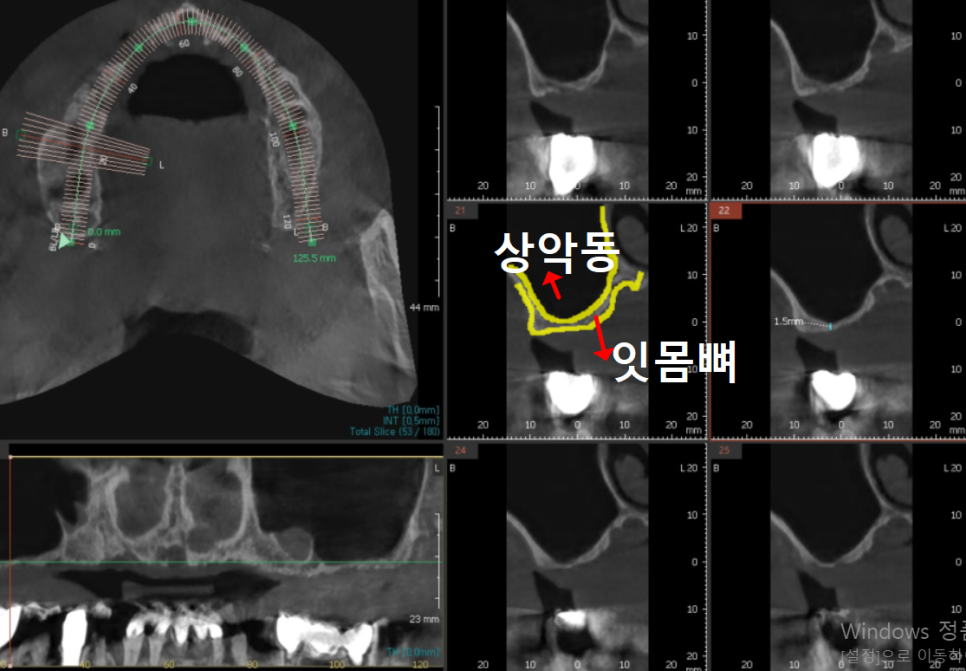

사진상에서 보면 이 부위가 상악동인데,

까맣게 보이는 이유는 안이 뻥~ 뚫려 있기 때문이죠.

그런데 이 환자분은 1.5mm밖에 남지 않은 상태였습니다.

CT도 같이 살펴볼게요.

노란색으로 표시한 잇몸뼈 부분,

눈으로 보기에도 굉장히 얇죠?